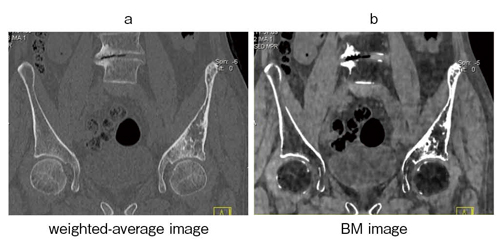

●骨悪性リンパ腫の治療後

当院にて診療中の72歳,男性の骨悪性リンパ腫の治療効果をBM imageにて評価した(図3)。weighted-average imageでは,寛骨臼蓋から腸骨翼にかけて骨硬化が見られる(図3a)。BM image(図3b)を作成し骨髄の様子を観察すると,脂肪髄に変わっていることが確認でき,治療効果が得られたと判断できた。

図3 72歳,男性,骨悪性リンパ腫の治療後